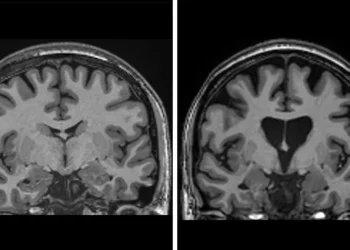

Alzheimeri mund të parandalohet! Ja katër shtyllat kryesore që e ulin rrezikun e demencës në 40%

Aktiviteti fizik i moderuar, gjumi i rregullt, dieta dhe vaksinimet janë katër shtyllat kryesore që mund të ndihmojnë në parandalimin…